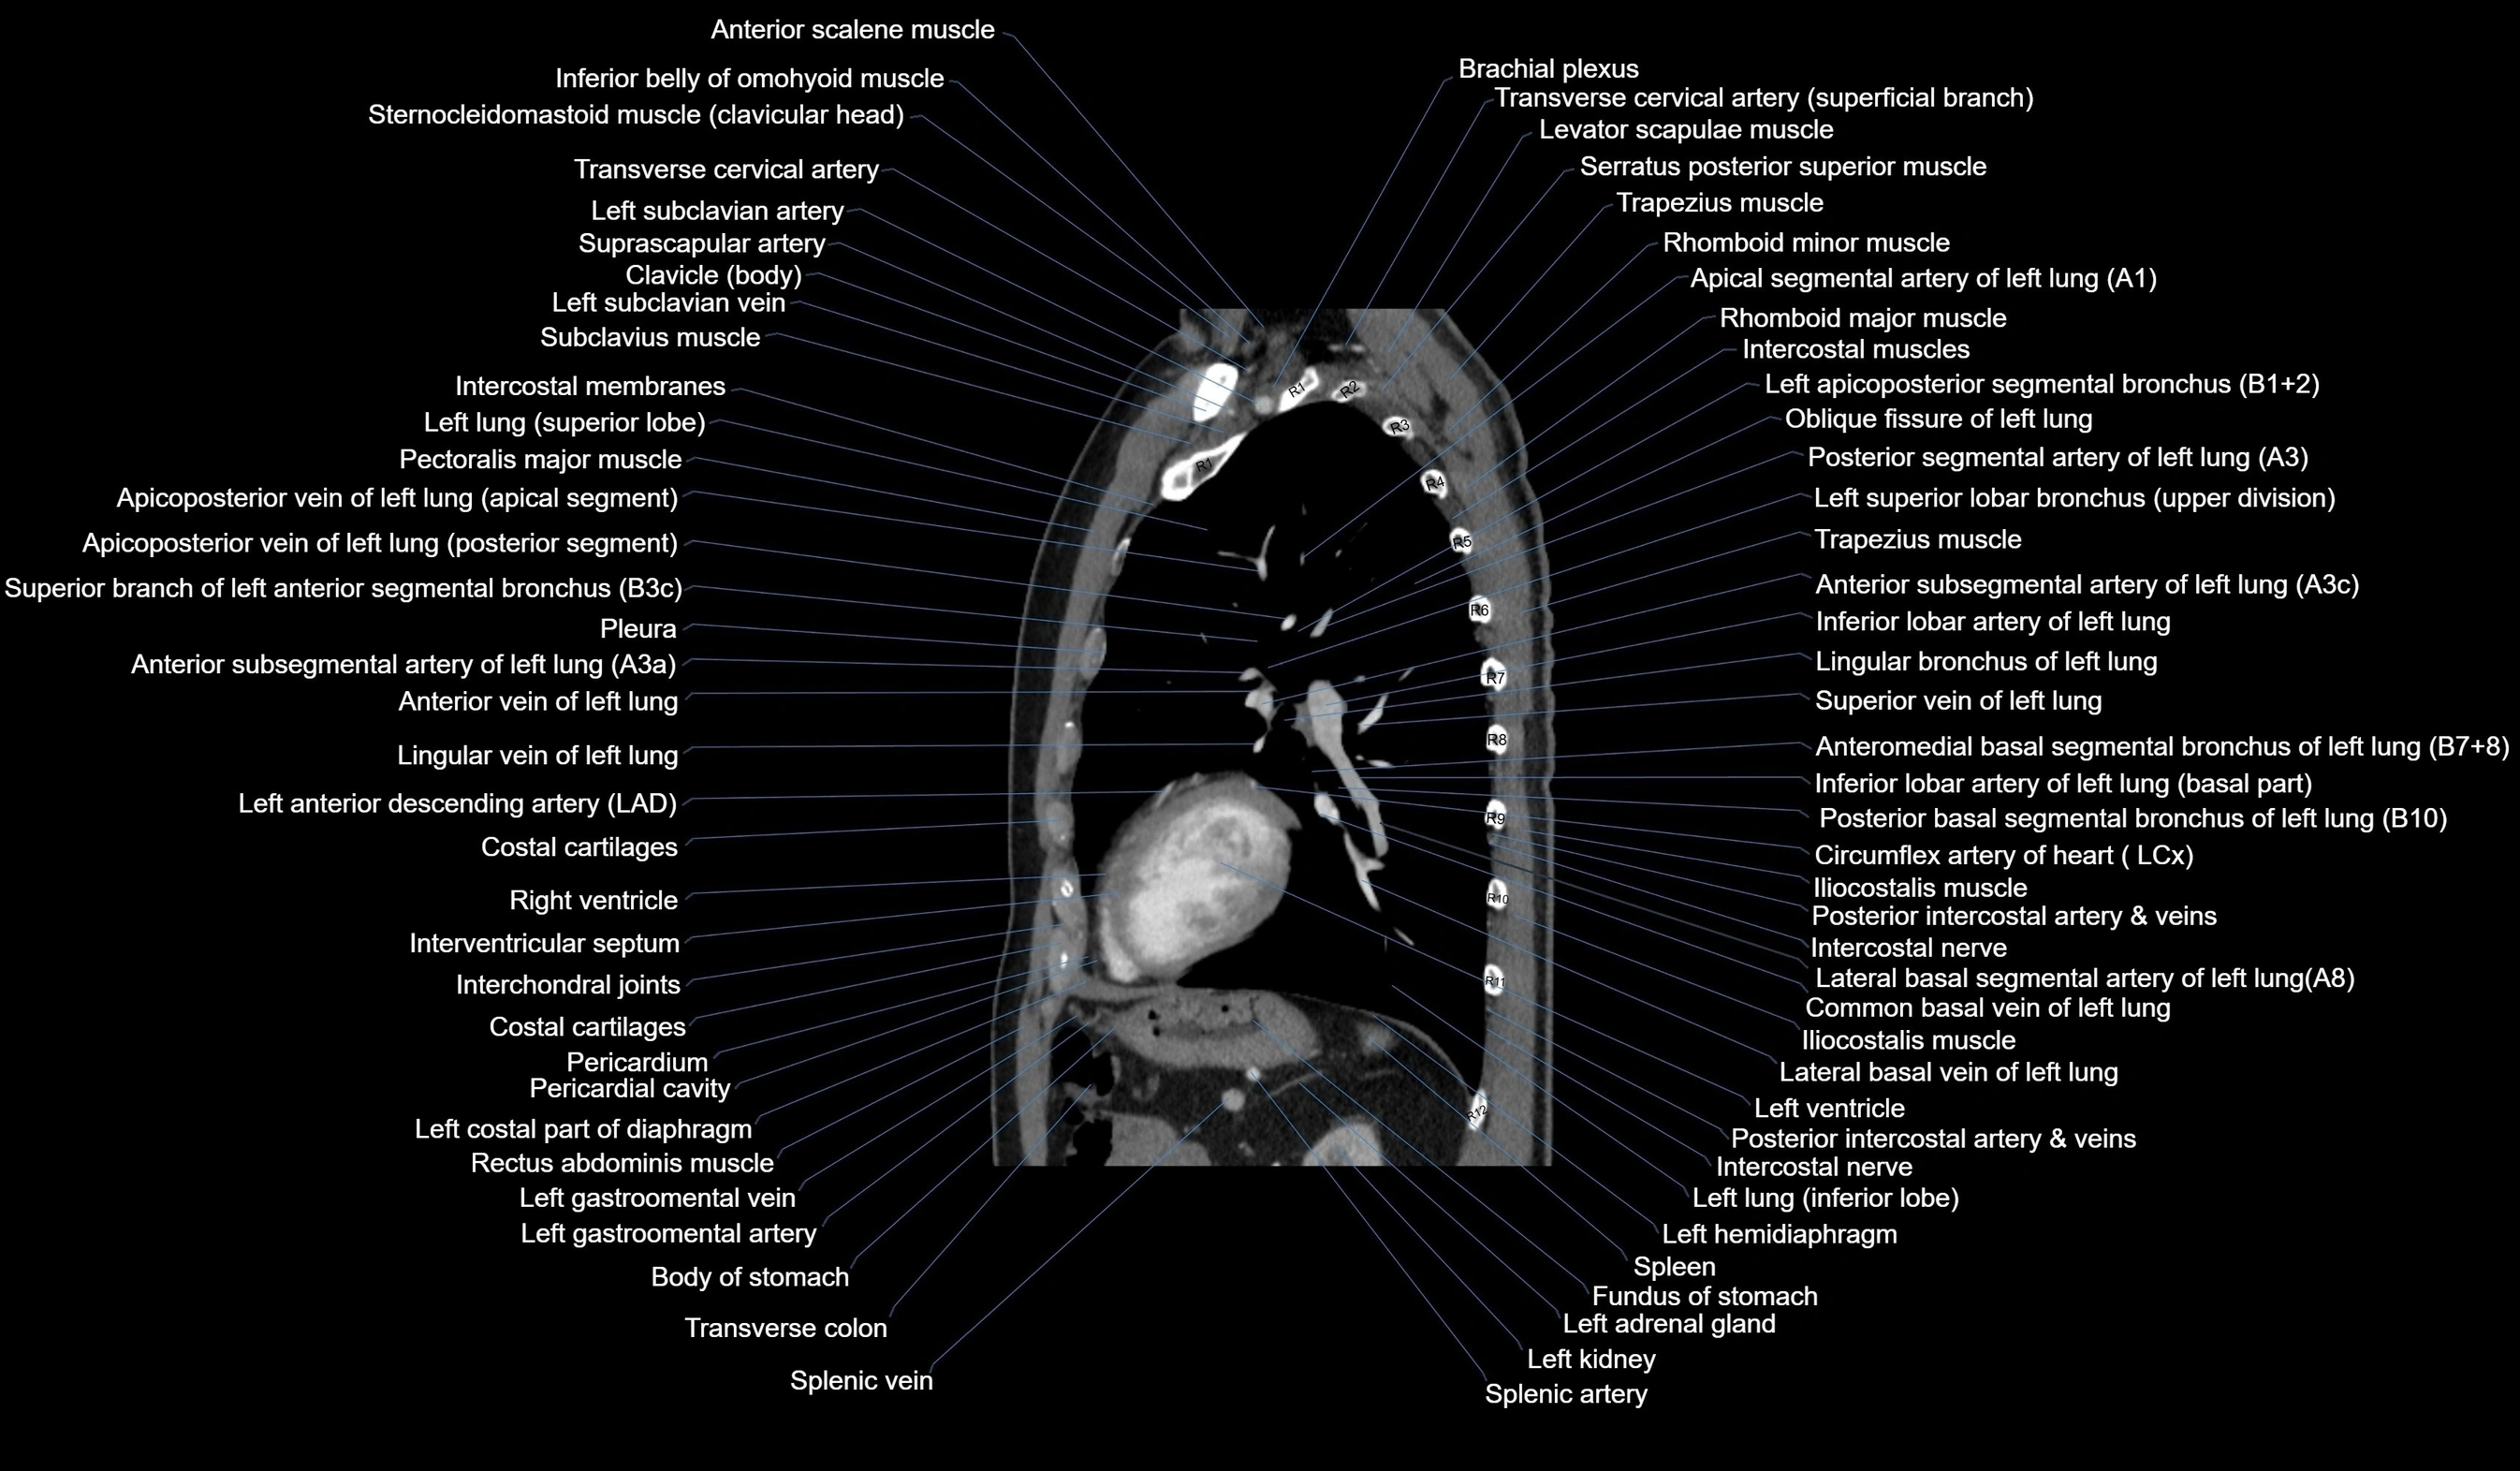

CT images